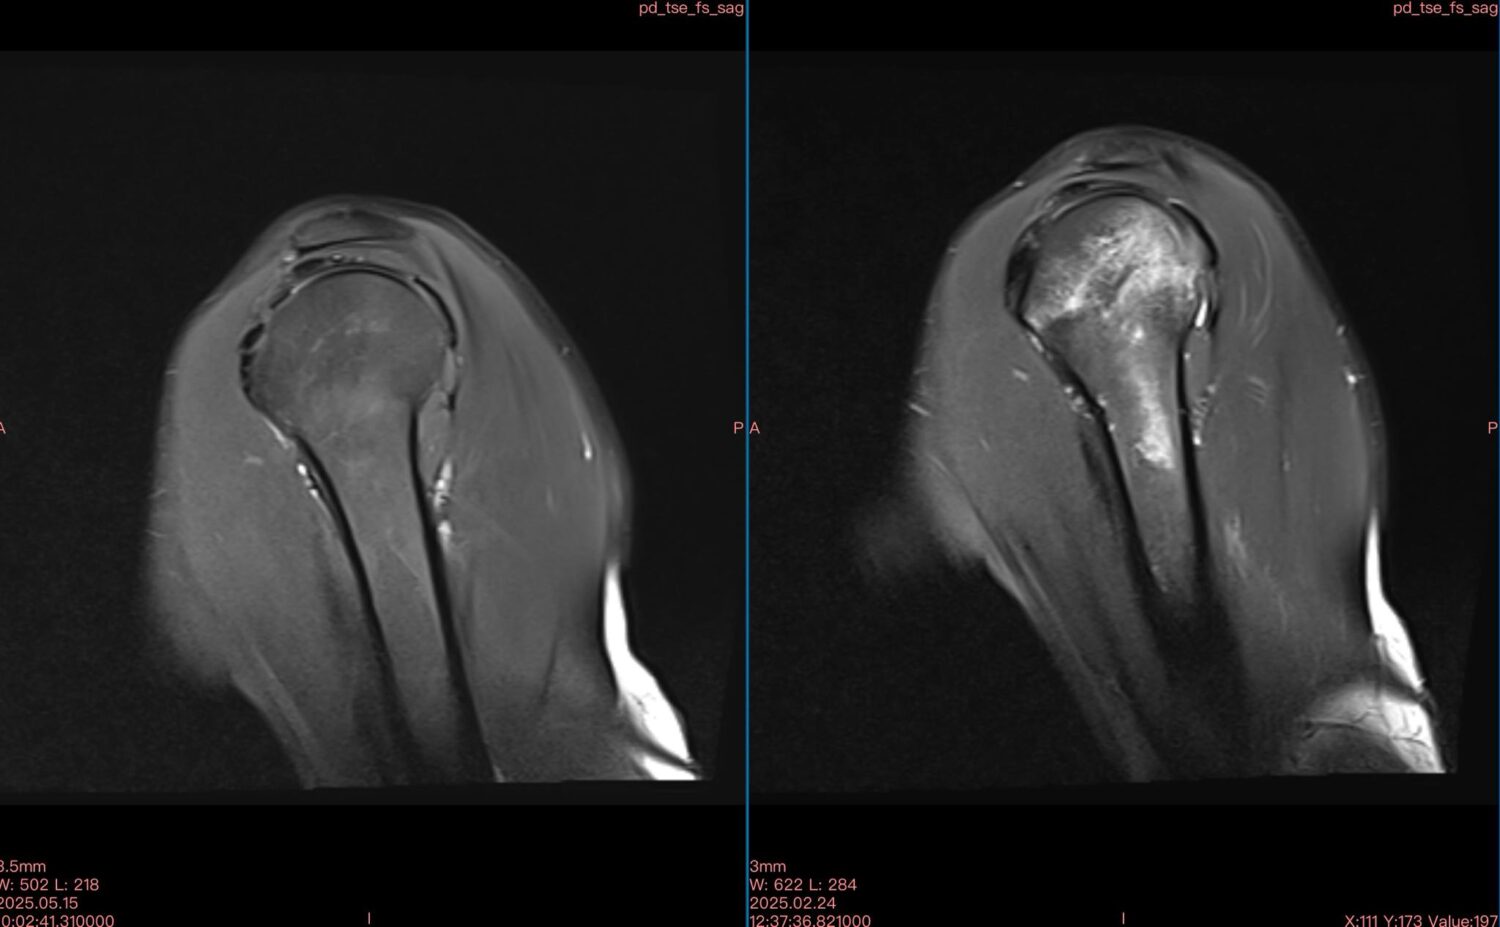

Μαγνητικές ασθενών με οστικό οίδημα πριν (αριστερή φωτογραφία) και μετά (δεξιά φωτογραφία) την θεραπεία με διαμαγνητική αντλία: